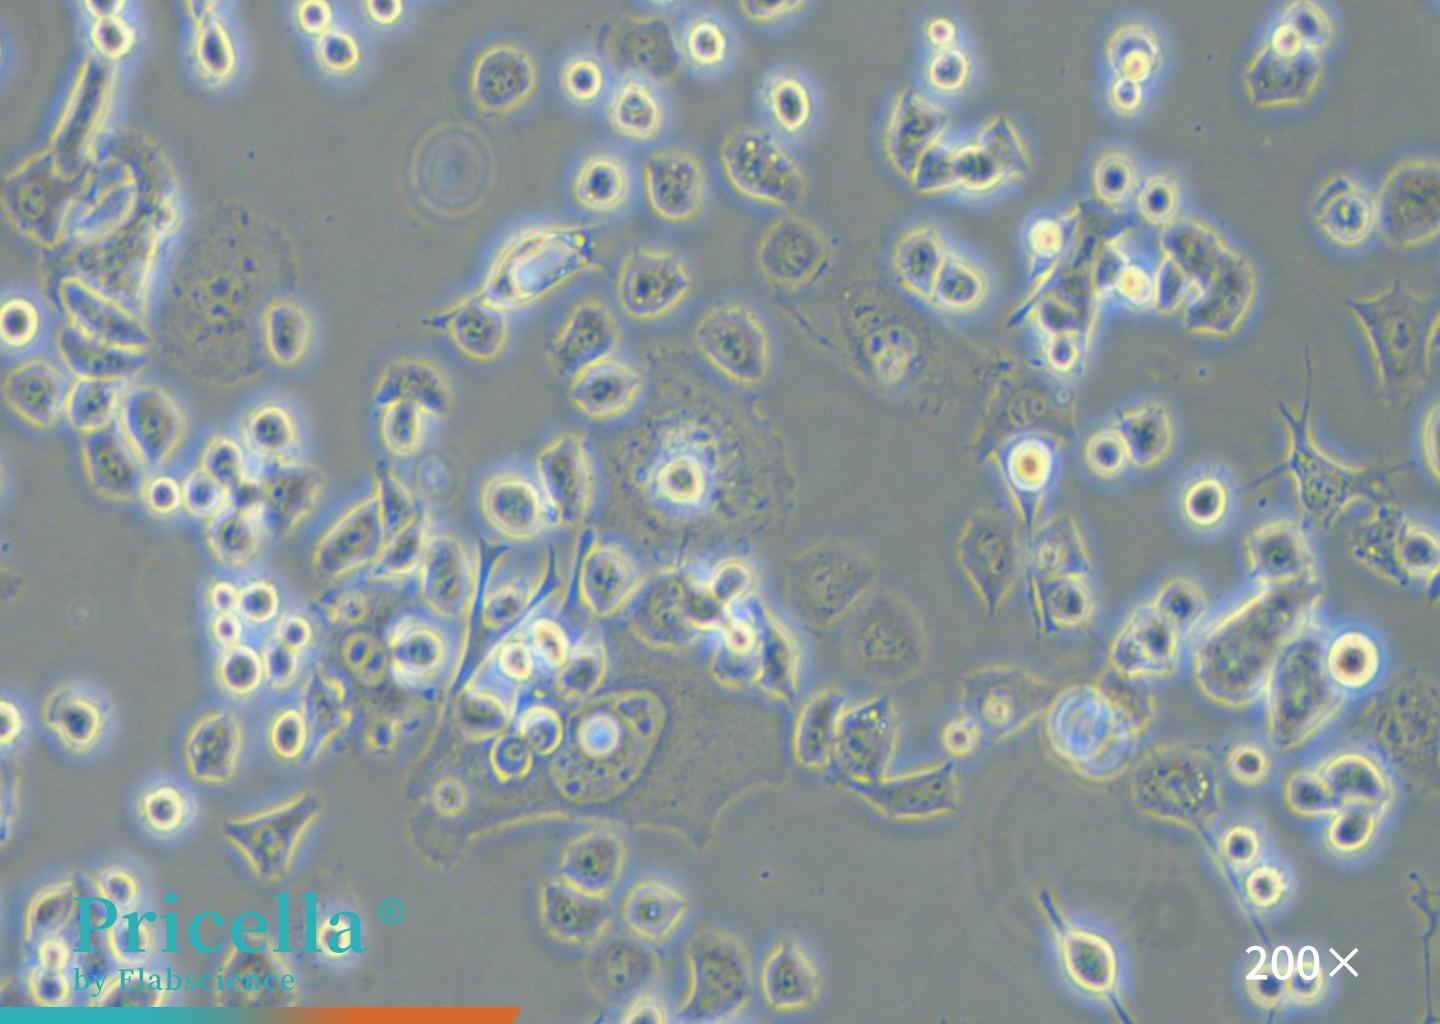

Figure 1. Microscopic Observation of SH-SY5Y

SH-SY5Y cells are a triply cloned subline derived from the human neuroblastoma cell line SK-N-SH. This lineage was originally established in 1970 from a metastatic bone tumor in a 4-year-old patient.

Undifferentiated SH-SY5Y cells exhibit continuous proliferation and express immature neuronal markers. Upon induction with agents such as retinoic acid (RA) or brain-derived neurotrophic factor (BDNF), they can differentiate into a neuron-like phenotype. Following differentiation, the cells reproduce key features of cholinergic neurons associated with AD and are widely used as in vitro models in neurodegenerative disease research[4].